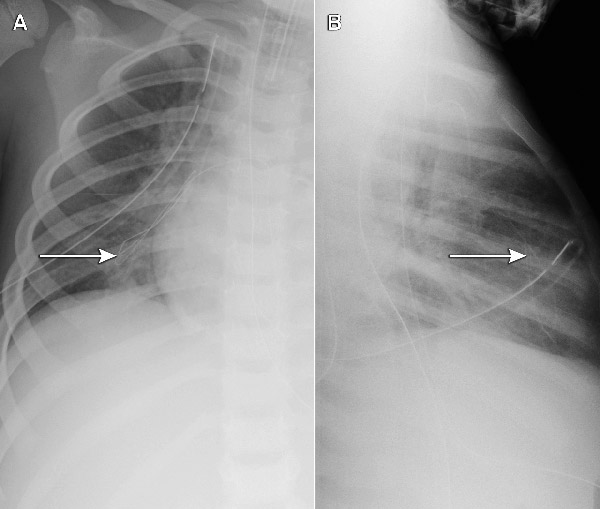

Each of the five cases identified was undetected at the time of insertion. As only part of the guide wire embolised, the portion withdrawn by the operator provided a false reassurance. The extremely fine embolised wires had not been noted on post-insertion chest x-rays (where the focus is usually on the position of the catheter tip), but were apparent when a specific review of the films was undertaken (Box 2). This cluster of five cases (involving different operators) at a single hospital triggered a statewide case review, through which an additional five cases in two further hospitals were reported (one actual embolus and four “near misses”, where the wire unravelled, but was noticed and retrieved before entering the patient). All involved the same type of device, giving a total of 10 cases at three hospitals out of 710 patients followed up. Although objective data about whether the wire was cut in every case were not available (because it can be cut without detection), at least one clinician was certain the wire had not been cut.